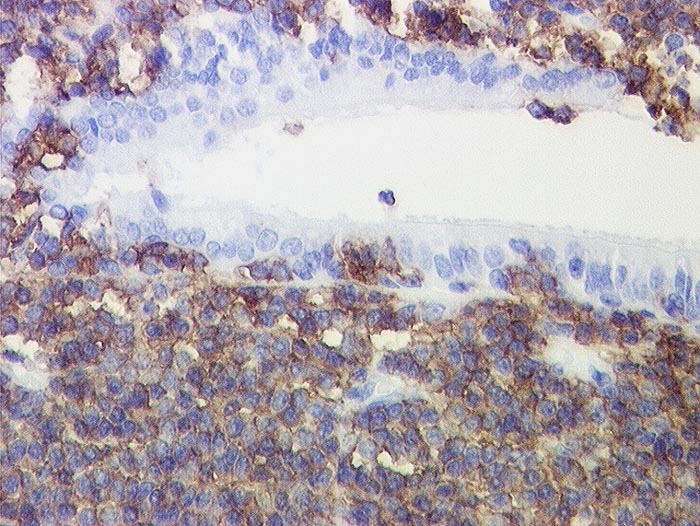

Marginalzonenlymphom vom MALT Typ: Lymphoepitheliale Läsion

In der Bronchialschleimhaut Gruppen von mehr als 5 Lymphomzellen. Diese reagieren positiv mit dem B-Zell Marker CD20. Die subepithelial gelegenen Lymphomzellen reagieren ebenfalls positiv.

Histologie

Immunhistochemie

CD20 (L26)